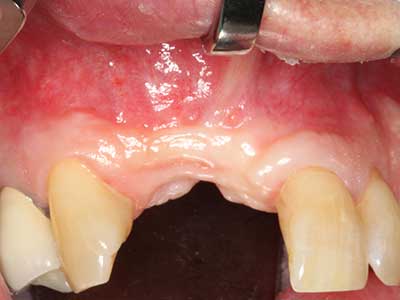

Fig. 2: Defecto del maxilar superior lateral vertical y horizontal con línea de la sonrisa alta, con indicación para la reconstrucción antes del implante.

Fig. 3: La separación basal del bloque se ve facilitada con piezas dotadas de una angulación especial.